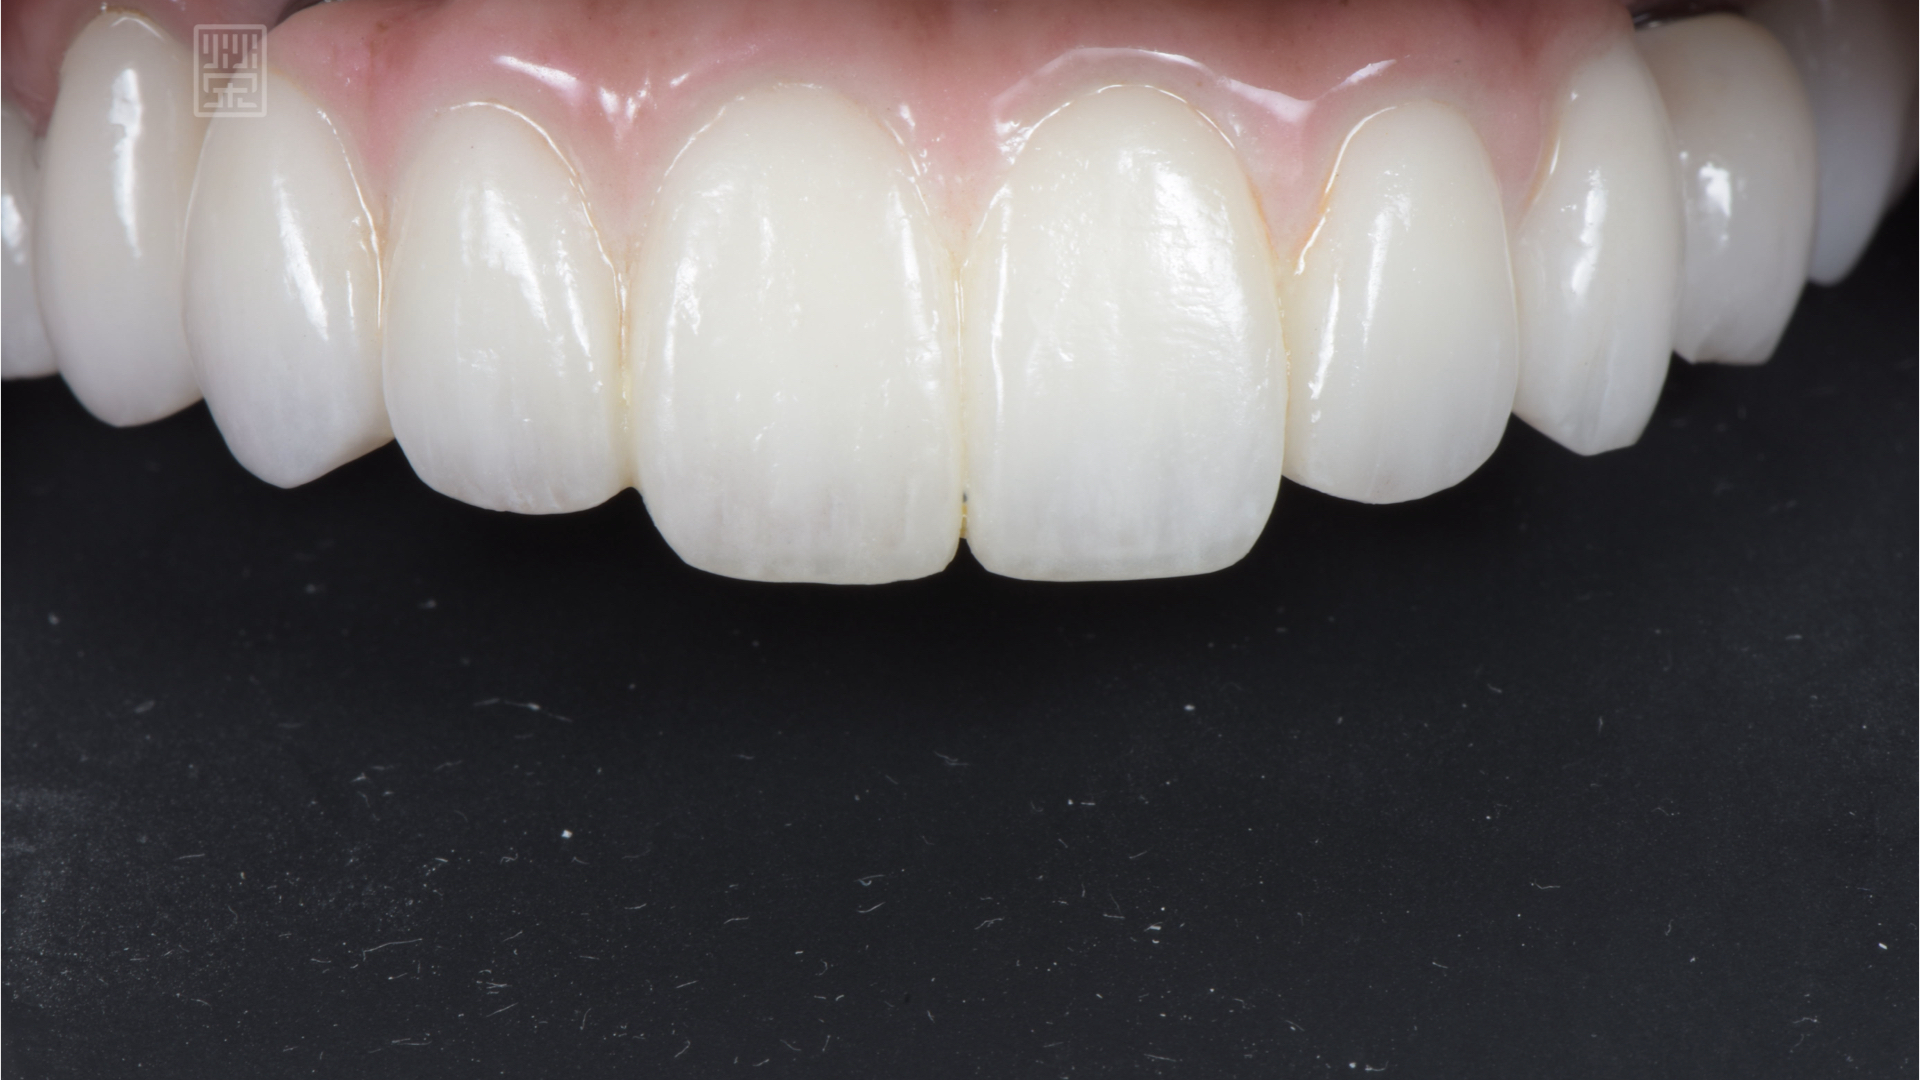

玻璃陶瓷貼片改變下顎門齒顏色與型態

全瓷贋復物完成